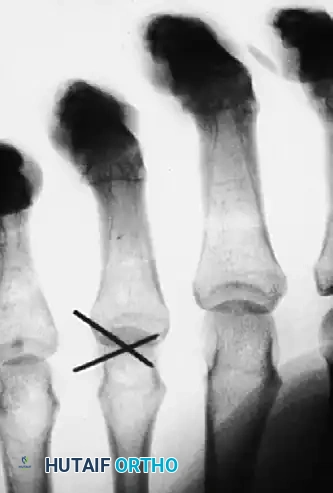

FIGURE 67-39 A: Radiograph of the hand of a 20-year-old man who sustained a horizontally directed fracture of the fourth metacarpal head. Note the palmar fragment displaced proximally, disrupting the cam mechanism.

FIGURE 67-39 B: The fracture was reduced via an open approach and held in place with multiple crossed Kirschner wires. While K-wires provide provisional stability, they lack interfragmentary compression.